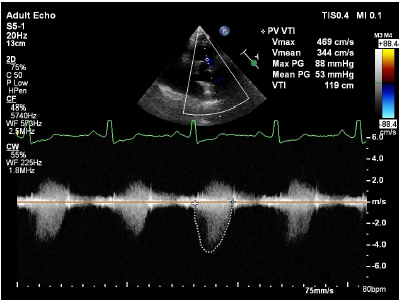

Transthoracic echocardiography showed dilated right atrium, right ventricle with a large atrial septal defect (ASD) with bi-directional shunt and severe pulmonary valve stenosis (Figures 2–4). Bubble's study confirmed the diagnosis of atrial septal defect (Figure 5) Parasternal long-axis view M-mode showed right ventricular hypertrophy of 9mm (Figure 6). Further plan for trans-esophagealechocardiography was discussed with patient but due to financial constraints as a foreigner, he decided to continue investigations in his home country. The patient was rehydrated with intravenous fluid therapy and was discharged with referral letter to home country.

Figure 4 Severe pulmonary valve stenosis.

Combination of severe pulmonary stenosis with the large atrial septal defect was “physiologically protective” where it prevented significant left to right shunt due to right ventricular outflow tract obstruction by severe pulmonary stenosis.5 However, the persistence of this condition has deleterious effects on right ventricular systolic function and this indicated that total surgical correction is indicated.5 Indication for operation for pulmonary valve stenosis is symptomatic or resting gradient of more than 40mmHg.6 Indication for atrial septal defect closure for patient of any age is hemodynamically significant defect where Qp/Qs >1.5. In our case, our patient has a large ASD with severe pulmonary stenosis of 88mmHg peak pressure gradient.